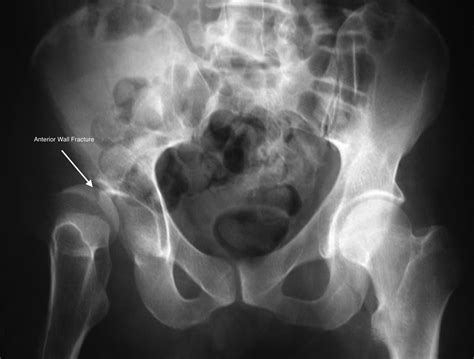

Diagnosis of Fractures of the Acetabulum

Diagnosing fractures of the acetabulum involves a combination of clinical examination and imaging studies. The diagnostic process typically includes:

• Clinical Examination: Assessing the patient’s pain, swelling, and range of motion in the hip joint.

• Imaging Studies:

• X-rays: Initial imaging to visualize the fracture pattern and assess the extent of the injury.

• CT Scans: Providing detailed images of the acetabulum and surrounding structures, essential for surgical planning.

• MRI: Occasionally used to evaluate soft tissue injuries and assess the condition of the femoral head.

Accurate diagnosis is crucial for determining the appropriate treatment plan and ensuring the best possible outcome for the patient.